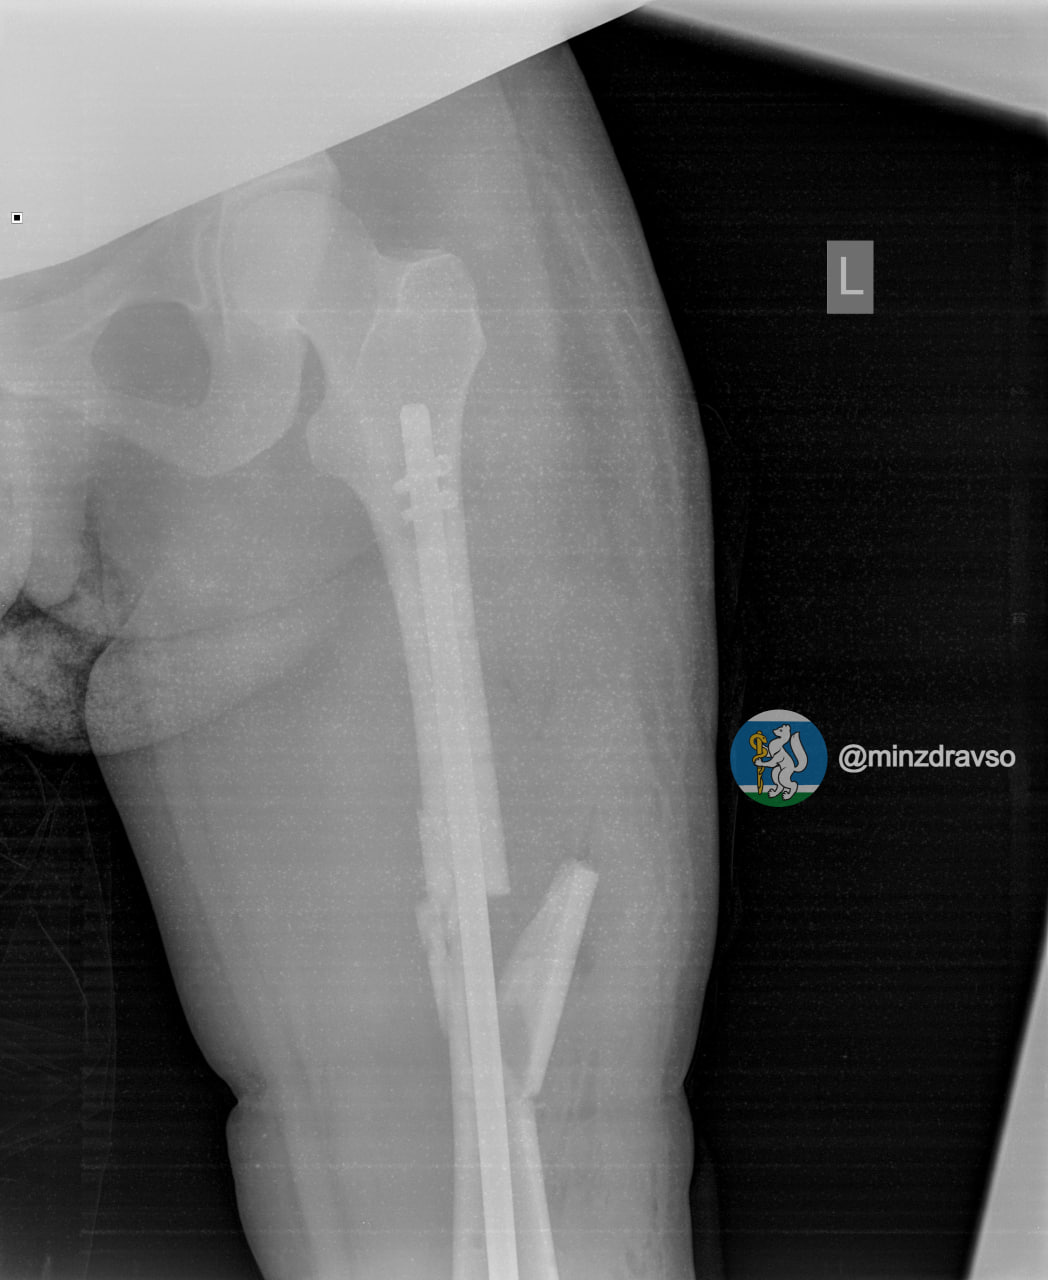

У нее диагностировали ушиб головы и сложный оскольчатый перелом левой бедренной кости.

Первую операцию свердловчанке провели экстренно в условиях шоковой операционной приёмного отделения.Через неделю, когда состояние женщины стабилизировалось, врачи смогли приступили к операции по замене аппаратов внешней фиксации на внутренний фиксатор. Ей был проведён блокирующий интрамедуллярный остеосинтез.